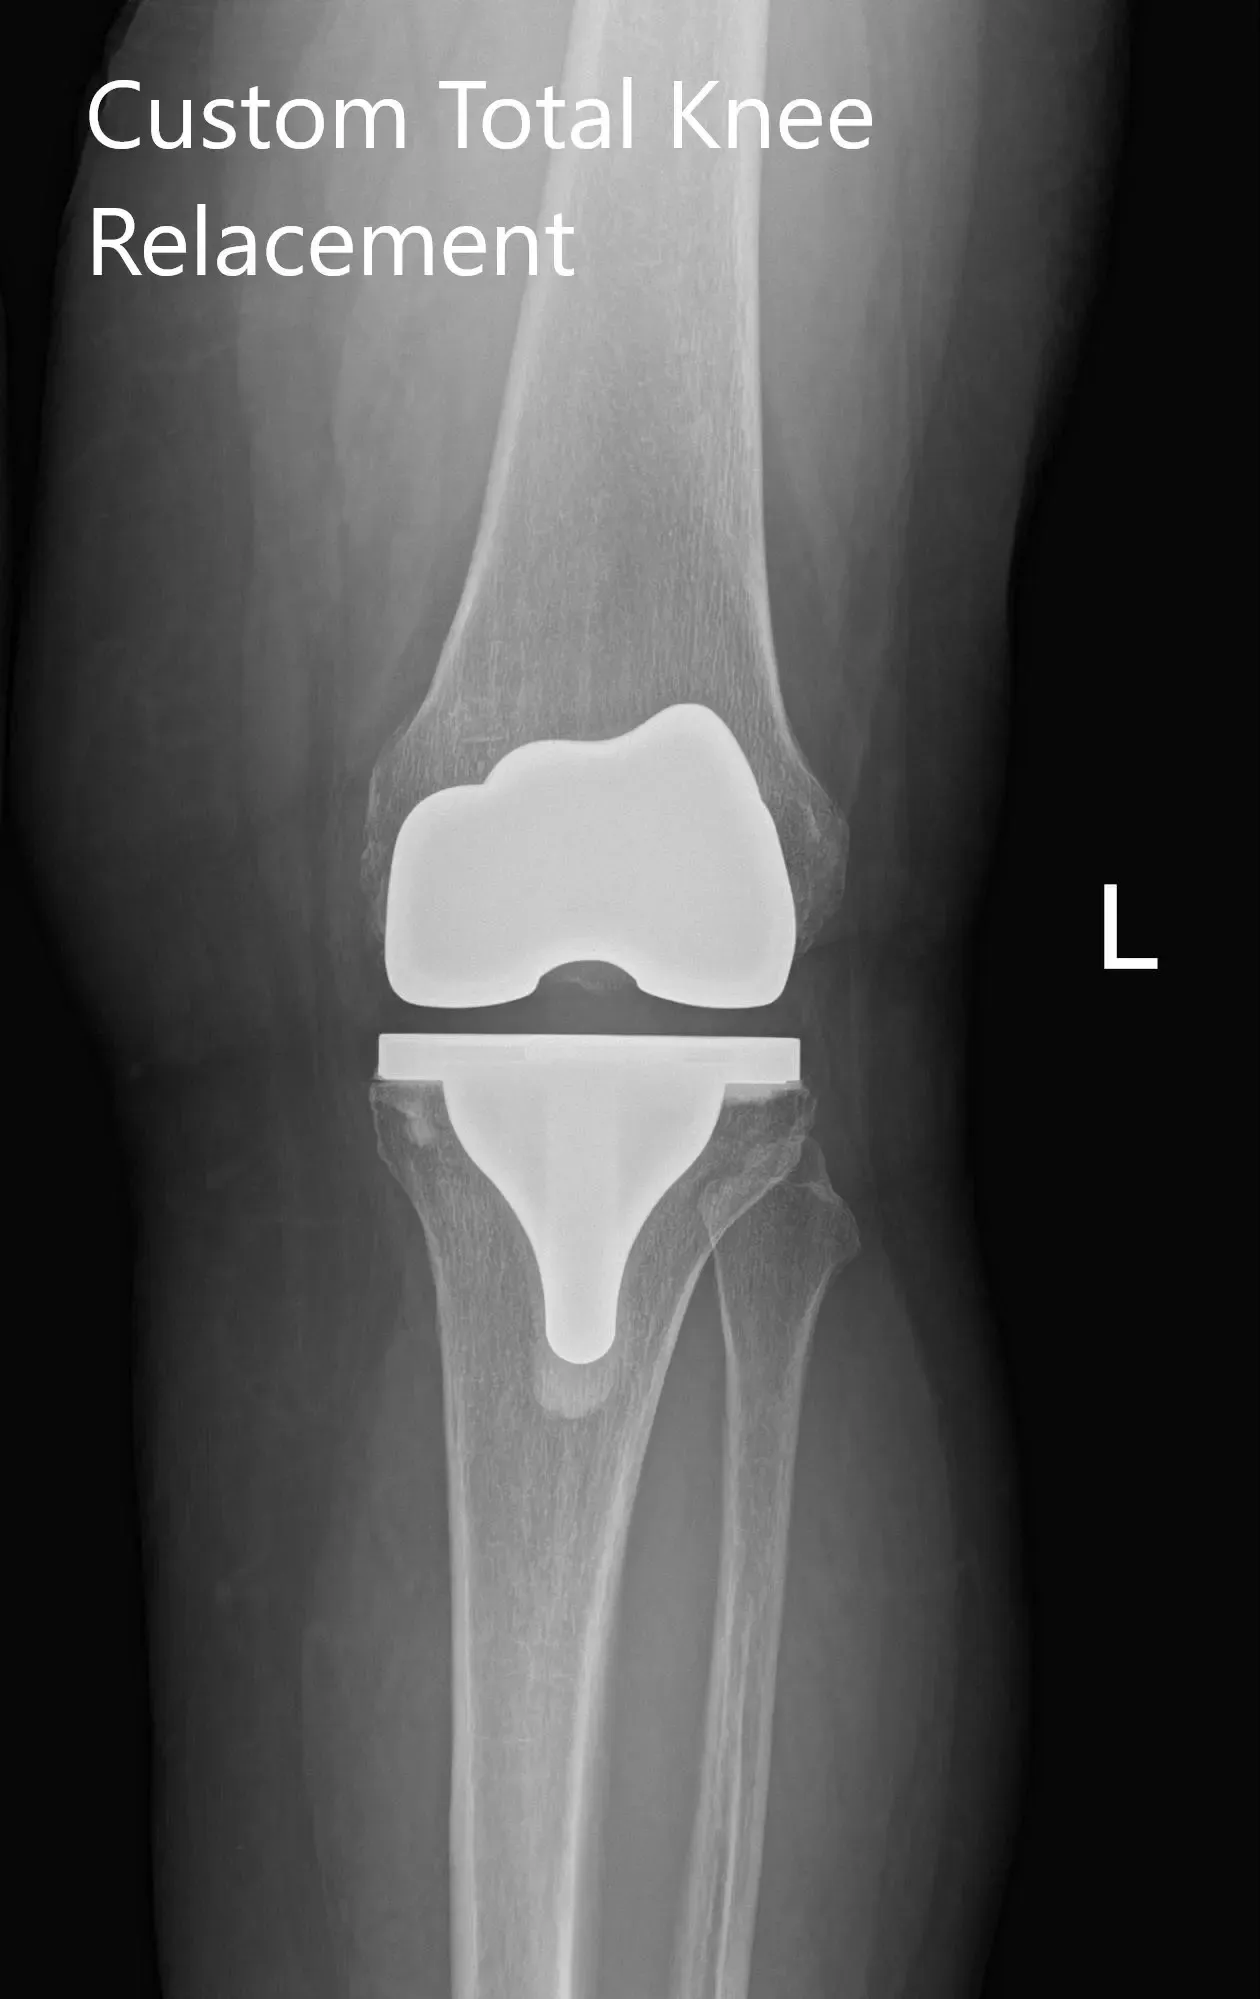

Post Operative X-Ray of the left knee showing AP and lateral view

Implants used: 8 mm posterior stabilized polyethylene with tibial tray, femoral implant 32 mm, 6 mm thickness polyethylene with an 8 mm polyethylene insert.